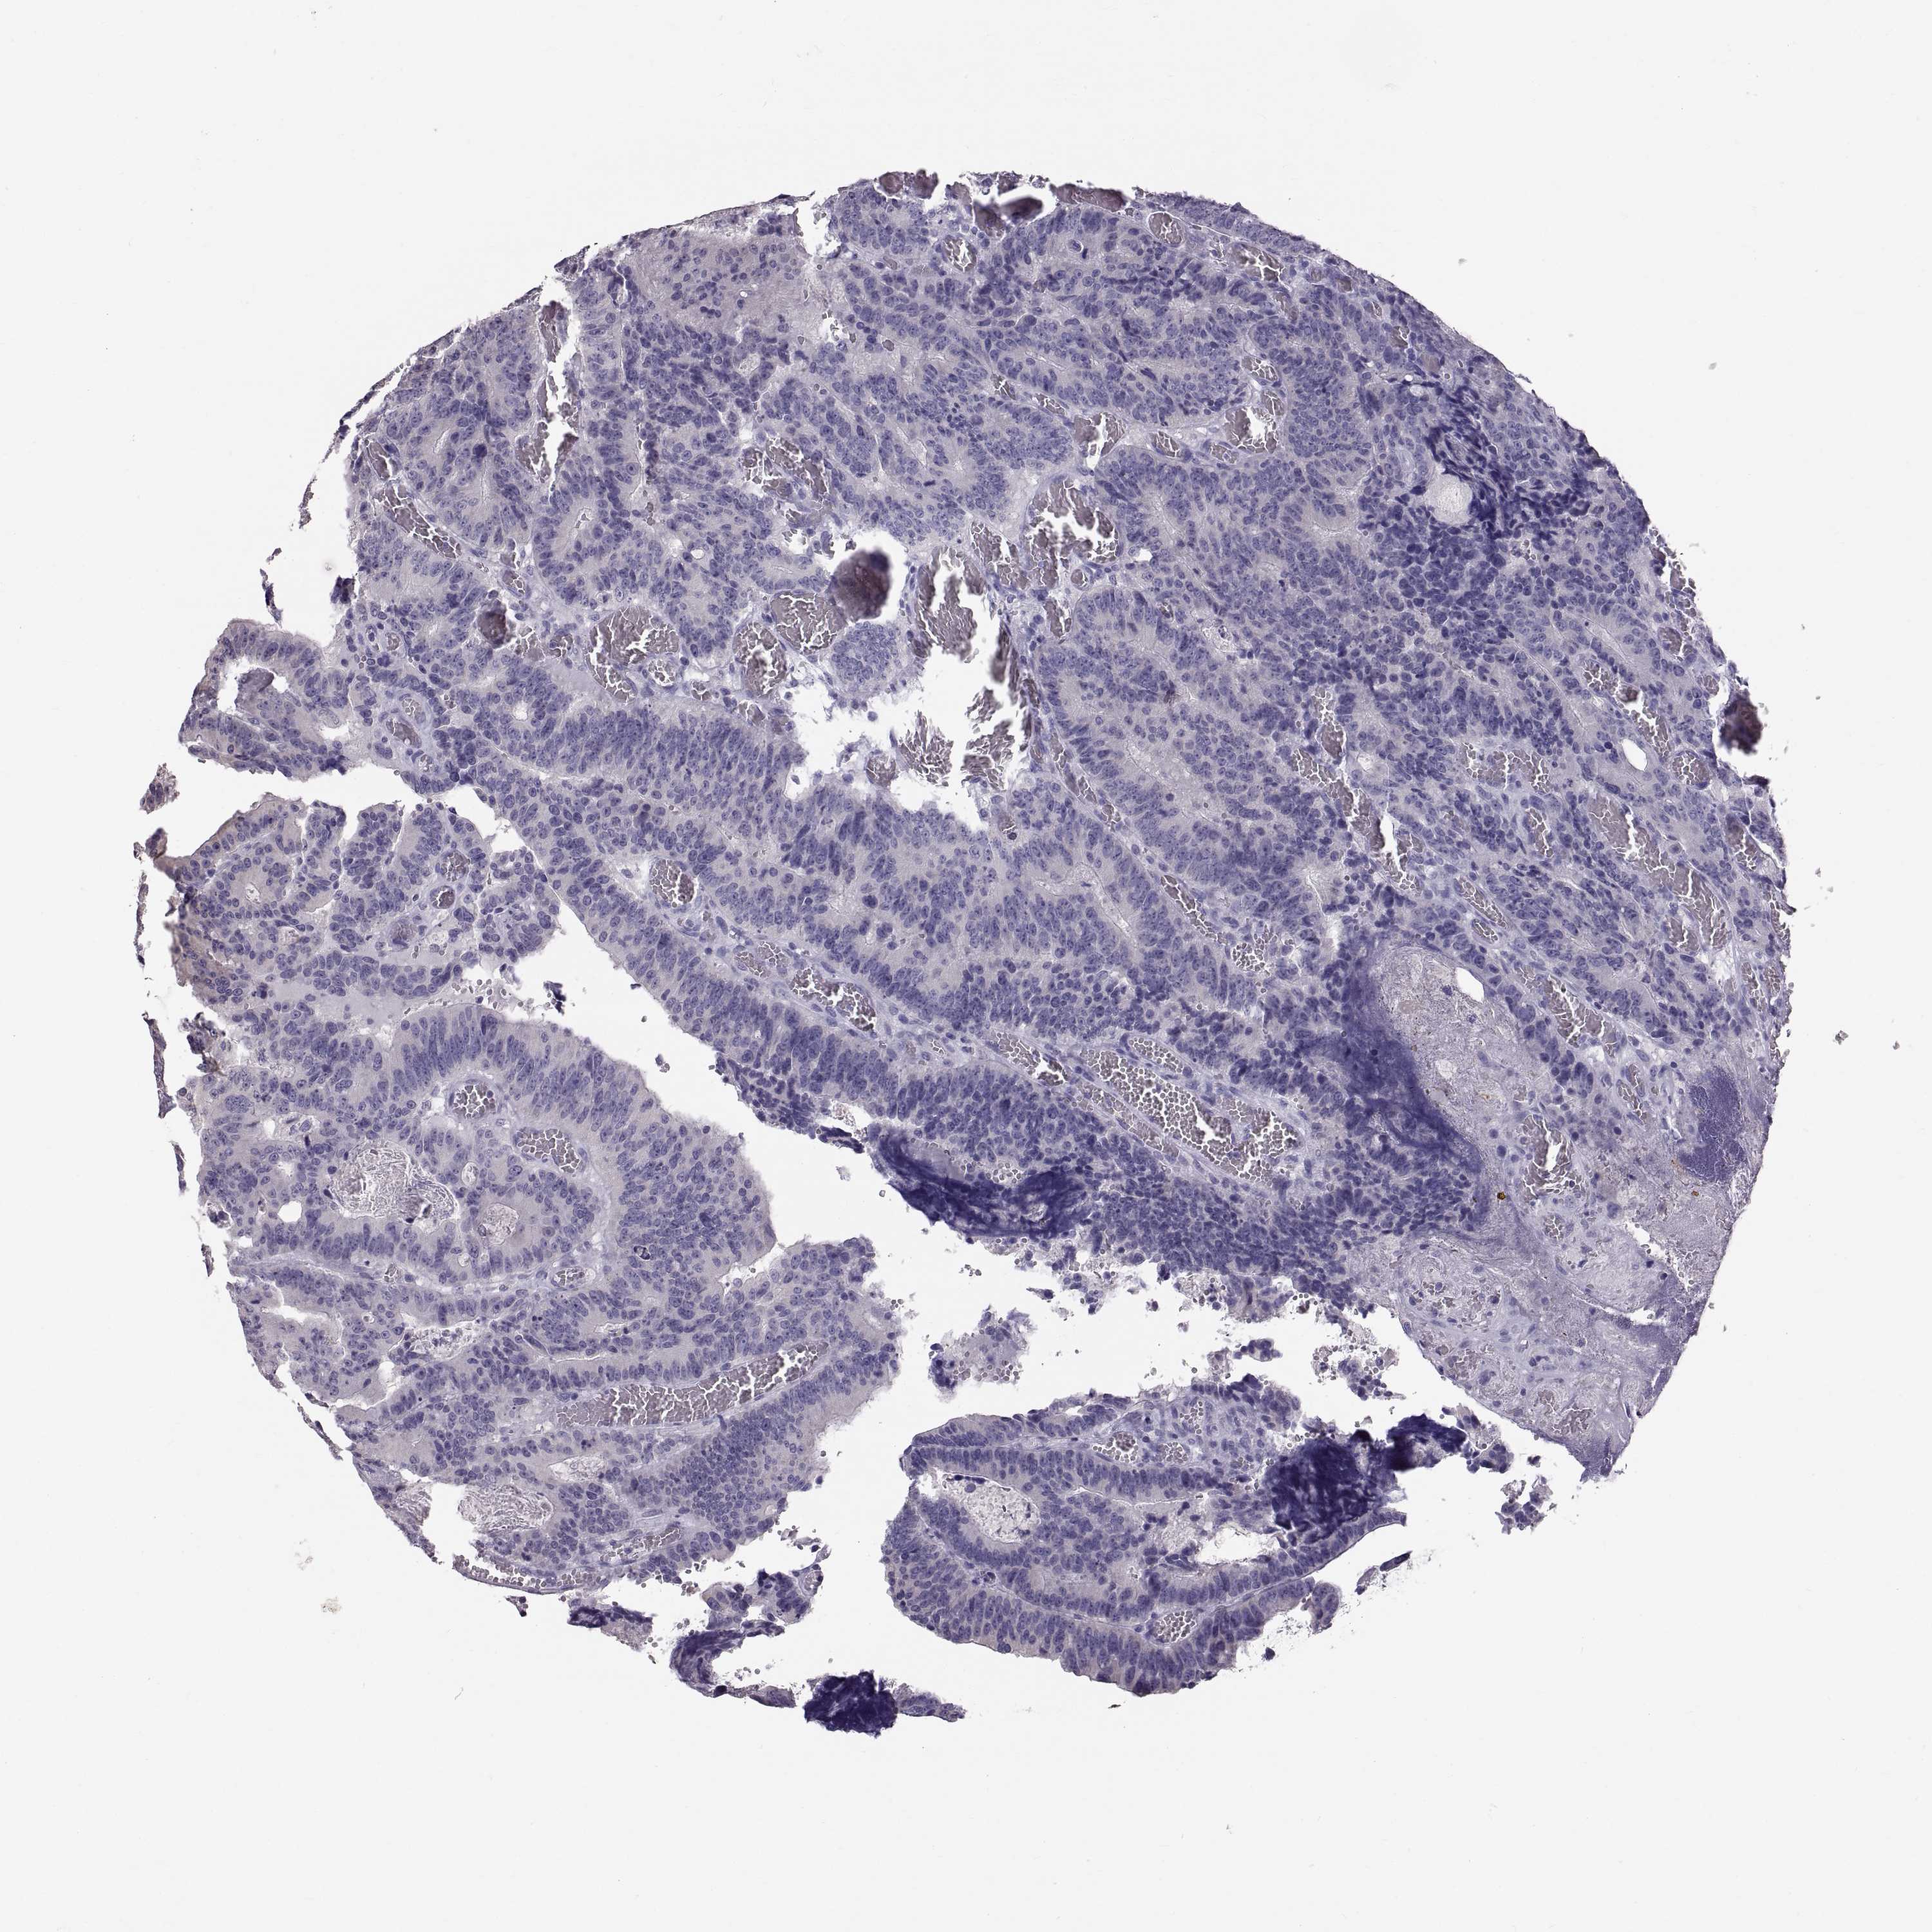

CANCER COLORECTAL CANCER Show tissue menu

Colorectal cancer

Colon adenocarcinoma